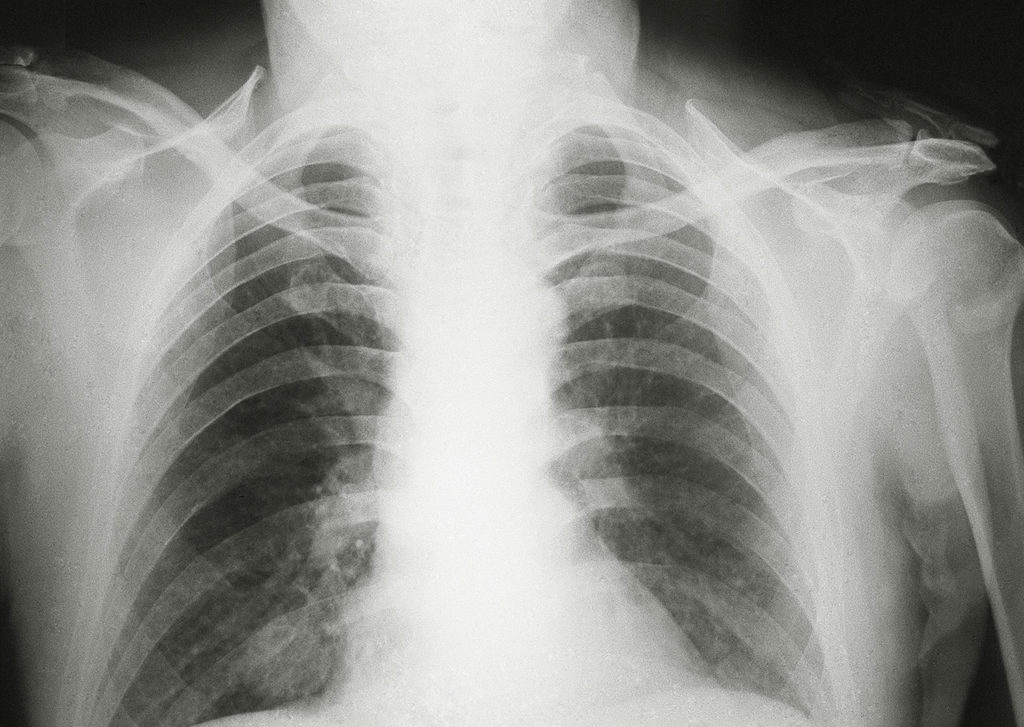

Диагностика рака легкого

Обследование на рак легкого включает в себя:

- биопсию;

- флюорографию или рентгенографию;

- по назначению врача также могут использовать компьютерную томографию (КТ), позитронно-эмиссионную томографию (ПЭТ), УЗИ, бронхоскопию (трахеобронхоскопию).